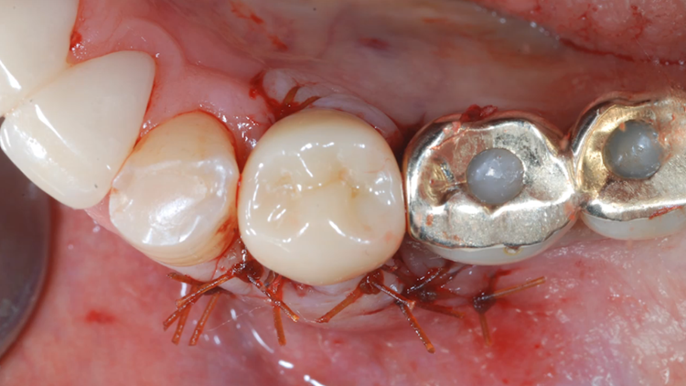

Clinical case: : Immediate loading of lower molars using R2Gate prefabricated 3D-printed provisional restoration

- Courtesy of Dr. Sam Omar, Egypt -

Keywords

Dr.Sam Omar, immediate loading, digital guided surgery, digital ONE-DAY implant, maxillary anterior, #21, guided surgery, immediate loading, AnyRidge, R2GATE, Mega ISQ, MEG Torq, R2GATE Full Surgical Kit

Products:

implant system, R2GATE Guide, R2GATE surgical kit (AnyRidge), Mega ISQ

“ONE-DAY implant, one-day smile

”